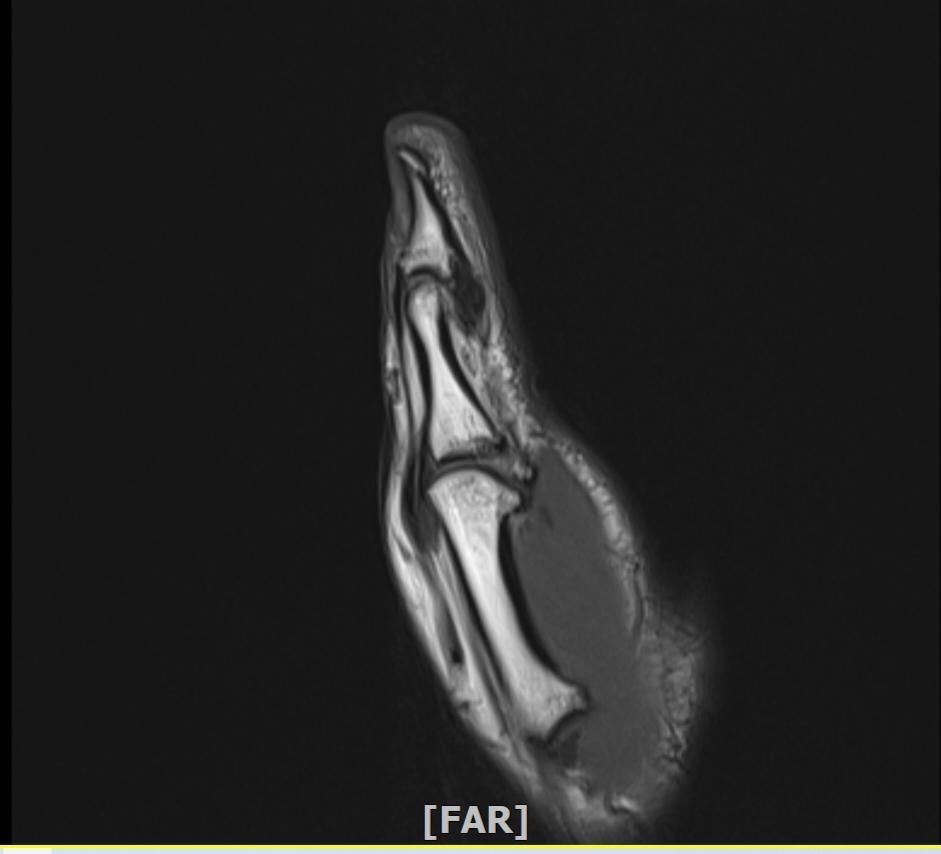

왼손 엄지손가락 부상 mri판독부탁드립니다

임팩에 장갑이 말리면서 엄지도 같이 말렸습니다

현재 손이 가끔 욱씬거리고 평소보다 뻣뻣하며 불안정감이 있는듯 합니다. mri사진으로 판독 가능하실까요 감사합니다.

• 1번 째 사진

정확한 판독을 하긴 어렵지만 연부조직의 주변부의 염증이 보여집니다.

올려주신 사진 상에서는 특별하게 큰 문제가 없을 수 있으나 부상과정에서 인대나 힘줄에 발생했던 부상으로 인해 긴장감이나 움직임 제한, 통증이 나티나는 경우에는 치료를 받아보시는 것도 좋겠습니다.

Mri 판독은 영상 전문의가 직접 이미지를 확인해야 정확하지만 엄지 부상 후 욱씬거림과 뻣뻣함, 불안정감은 인대 손상이나 골절, 건초염 가능성을 시사합니다. Mri에서는 인대 파열, 연골 손상, 골수 부종 등을 중점적으로 평가합니다. 증상이 지속되면 정형외과 전문의에게 영상 판독과 임상 진단을 반드시 받는 것이 안전합니다!